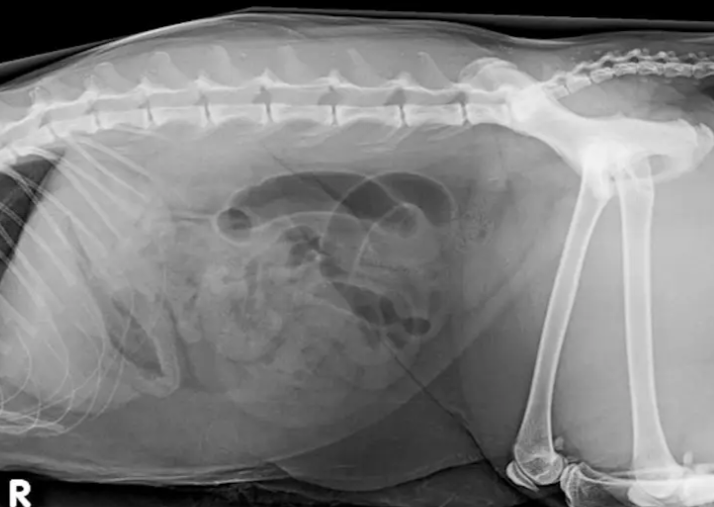

L'échographie est un merveilleux outil de diagnostic en pratique vétérinaire mais est-elle toujours la modalité la plus appropriée? La radiologie a perdu un peu de son glamour ces dernières années, dépassée par d'autres modalités, mais elle reste un outil essentiel dans tous les aspects de la pratique vétérinaire. Sa valeur ne doit pas être sous-estimée. Cette présentation passera en revue plusieurs scénarios cliniques où la radiologie l'emporte sur l'échographie et où la radiologie et l'échographie sont des tests complémentaires. Il y a bien sûr des situations cliniques où l'échographie est le test le plus approprié pour le patient. En utilisant une approche basée sur le système et le cas, ces choix seront explorés dans le but d'aider le clinicien à choisir la modalité d'imagerie la plus appropriée pour les patients présentant une plainte.